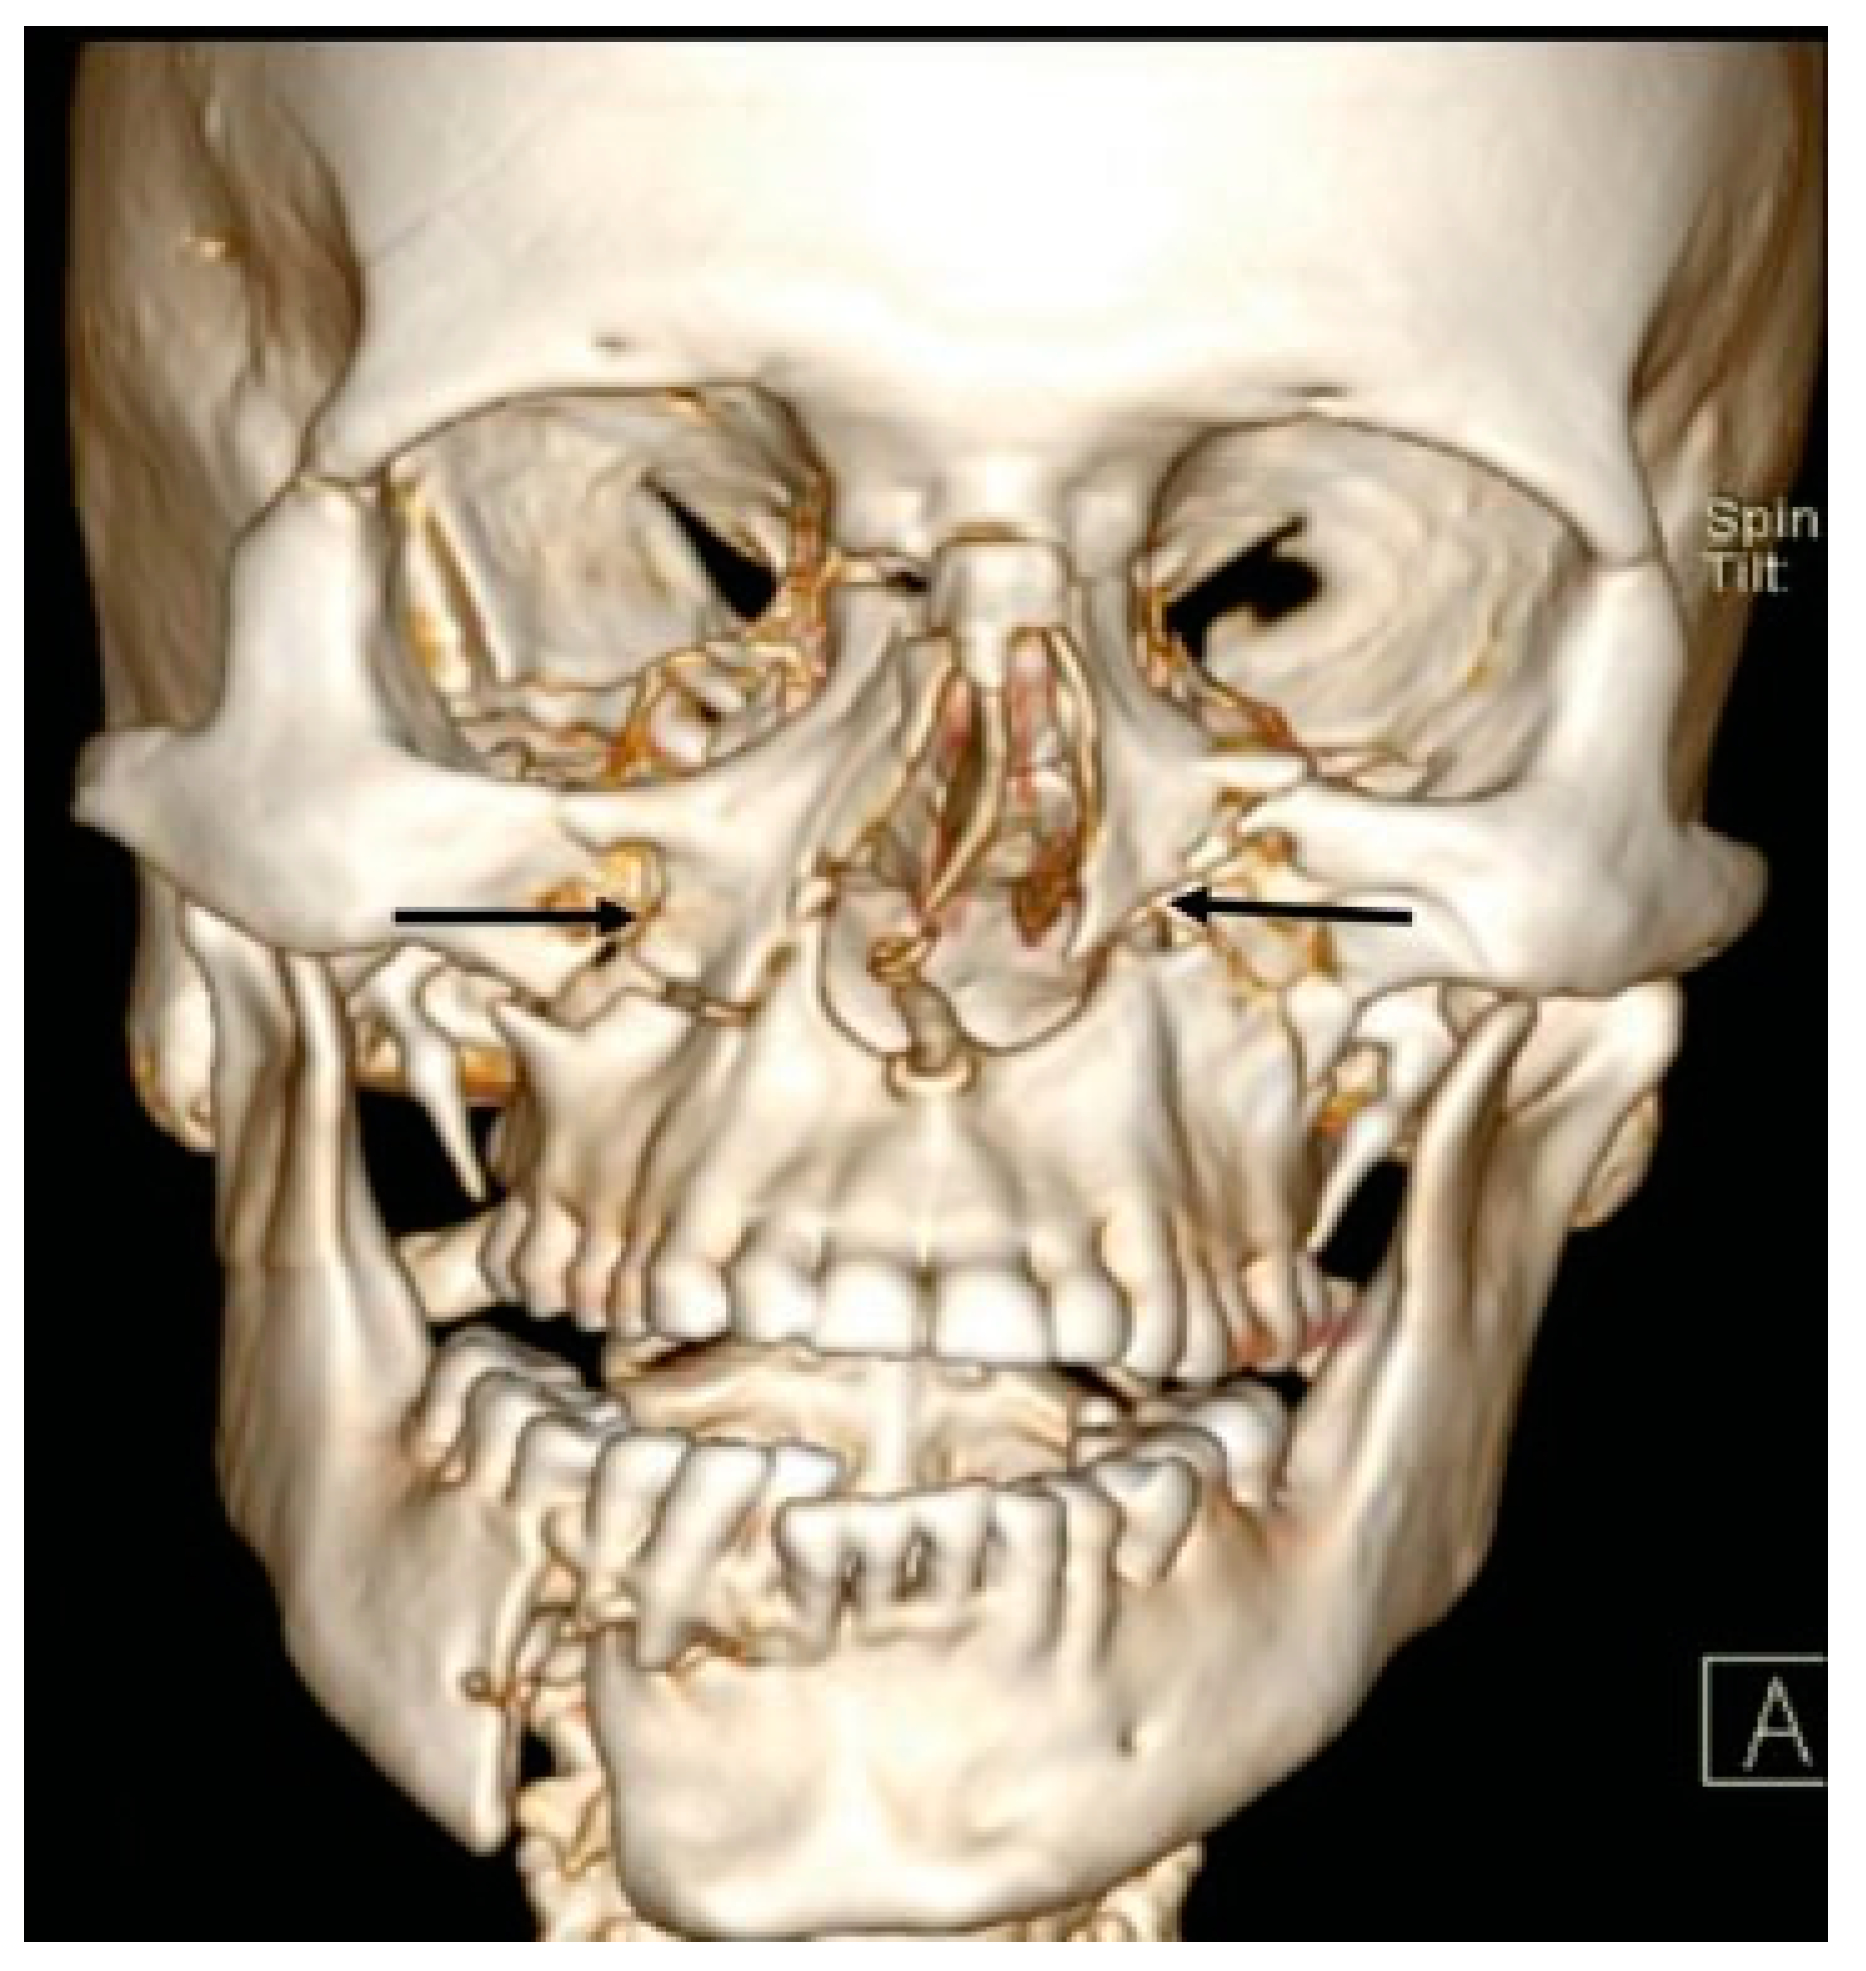

- Additional line extending from the infraorbital rim to the Le Fort fracture line.

- D2: Additional Line Extending from Infraorbital Rim to the Le Fort Fracture Line (25.4%)